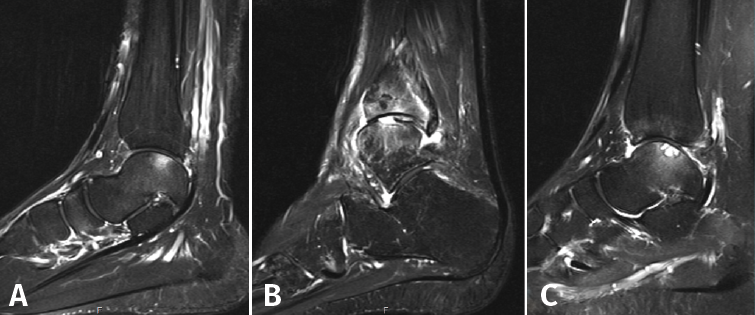

Otras clasificaciones están basadas en la tomografía axial computarizada (TAC) o en la resonancia magnética (RM) y engloban las LOC tanto agudas como crónicas. El estudio mediante TAC permite más precisión para definir el tamaño y la localización de las lesiones, así como de la presencia de cambios quísticos. Ferkel y Sgaglione desarrollaron un sistema de clasificación basado en la TAC (Figura 2), que tiene la particularidad de servir de apoyo para la planificación preoperatoria y la elección del tipo de tratamiento más adecuado (tornillo/pin, microfractura o injerto)(18).

Figura 2. Imágenes de resonancia magnética que muestran diferentes fases de lesión osteocondral. A: estadio IIA, que muestra edema óseo circundante; B: fractura osteocondral en estadio IV con un fragmento desprendido y desplazado; C: estadio V que muestra la formación de quistes subcondrales.

Hepple desarrolló un sistema de clasificación basado en la RM y que también tiene implicaciones de indicación (Tabla 2). Actualmente, la RM constituye el mejor método para evaluar la estabilidad de un fragmento mínimamente o no desplazado, lo que puede influir en la necesidad, o no, de practicar su fijación (Figura 3)(19,20).